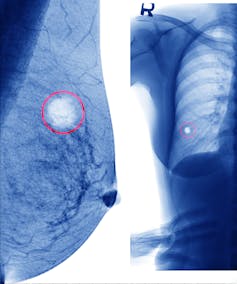

Breast cancer

Perhaps the highest-profile cancer, progress in breast cancer has been strong. However, 2,844 Australians, including about 30 men, still died of breast cancer in 2014 in Australia.

Breast cancer is now divided into different sub-types, each with its own behaviour. Understanding this has allowed more personalised therapy for many patients, which has improved treatment outcomes.

Mammographic screening has attracted some controversy because of possible over-diagnosis. But with participation rates well above 50%, and more cancers being detected at more curable stages, it has likely contributed to the rise of five year survivals to 90%.